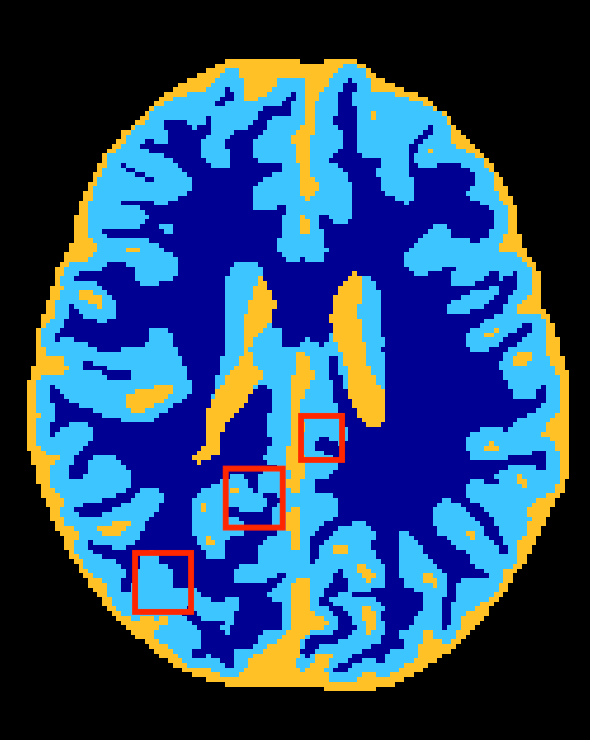

Figure 3 depicts visual results for the subject used in validation. It can be observed that HyperDenseNet (middle) recovers thin regions better than the baseline (left), which can explain improvements in distance-based metrics. As confirmed in Table 2, this effect is most prominent in boundaries between the gray and white matter. Further, HyperDenseNet produces fewer false positives for WM than the baseline, which tends to over-estimate the segmentation in this region.

Baseline

HyperDenseNet

Reference Contour